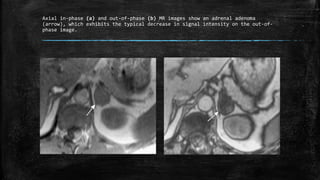

Axial in-phase (a) and out-of-phase (b) MR images show an adrenal adenoma

(arrow), which exhibits the typical decrease in signal intensity on the out-of-

phase image.